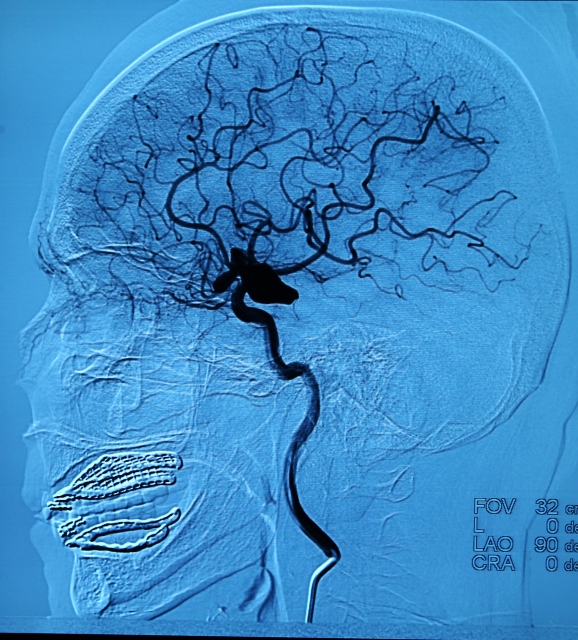

Aniden ortaya çıkan bir beyin fonksiyonu kaybı olan ve halk arasında felç olarak bilinen inmede, ilk 3 saatte yapılacak müdahale hayati önem taşıyor. 29 Ekim Dünya İnme Günü nedeniyle, Ankara Numune Eğitim ve Araştırma Hastanesi bünyesinde 2009'da kurulan "İnme Merkezi"nde, beyin kanaması geçirdikten sonra beyninde baloncuk oluşan hastaya yapılan müdahaleyi de görüntüledi.